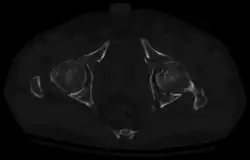

Axial CT image (viewed on bone windows) of a complex comminuted left acetabular fracture involving both anterior and posterior columns. -

To understand the fracture pattern of a fractured acetabulum, it is essential to have minimum three x-ray views, though use of CT scan with 3-D reconstruction of images has made understanding of these fractures easier.

In all cases, CT scan can assist in identifying impacted bone pieces, which may be found within the joint, and MRI may be done to identify the extent of potential injury to the sciatic nerve.